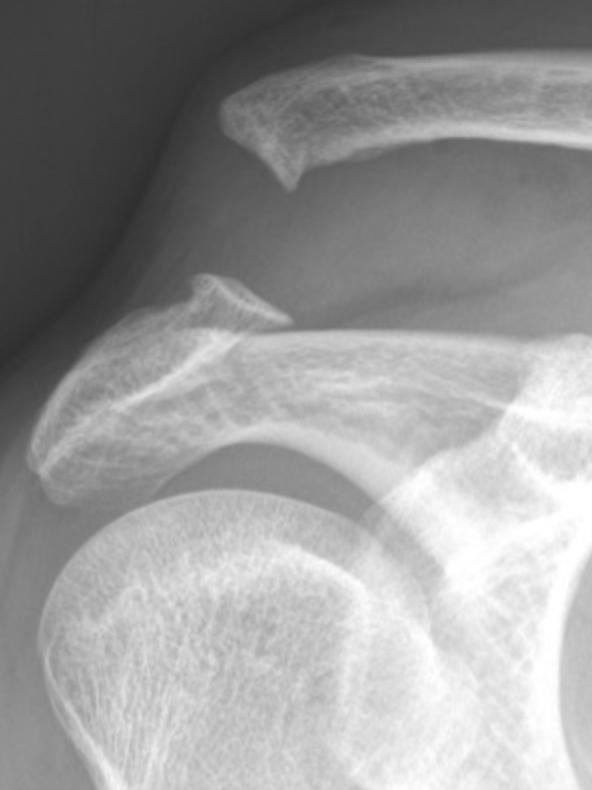

Glenohumeral Dislocation

Proximal Humerus Fracture